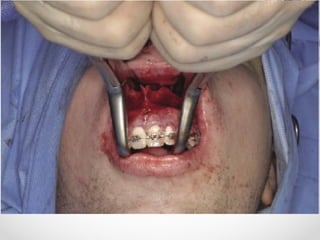

Internal Fixation

• Bone plates should be placed through intra-oral route wherever

possible

• External incisions are used for lower border of mandible & condylar

neck; also preferred in grossly resorbed edentulous mandible

• In simple mandibular #, mono-cortical 2mm plates provide

adequate fixation

• In ant mandible 2 plates are used while posteriorly one plate is

sufficient

• In complicated # with gross comminution, tissue loss, infection a

load bearing osteosynthesis with rigid internal fixation & bicortical

screws are required